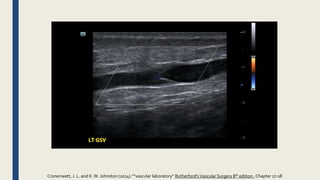

SuperficialVeinThrombosis

Contiguous extension

of the thrombotic process from the

superficial to the deep veins can occur

in three ways,

- most commonly from the great

saphenous vein (GSV) to the femoral

vein.

- Less often, the thrombus extends

from the small saphenous vein (SSV)

to the popliteal vein.

- Extension through perforator veins to

deep veins can also occur.